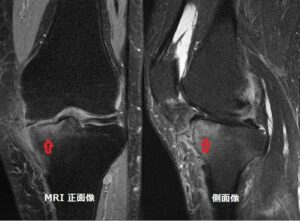

膝関節MRIでみられる骨髄浮腫 (bone marrow edema:BME)は、痛みの強さを表します。